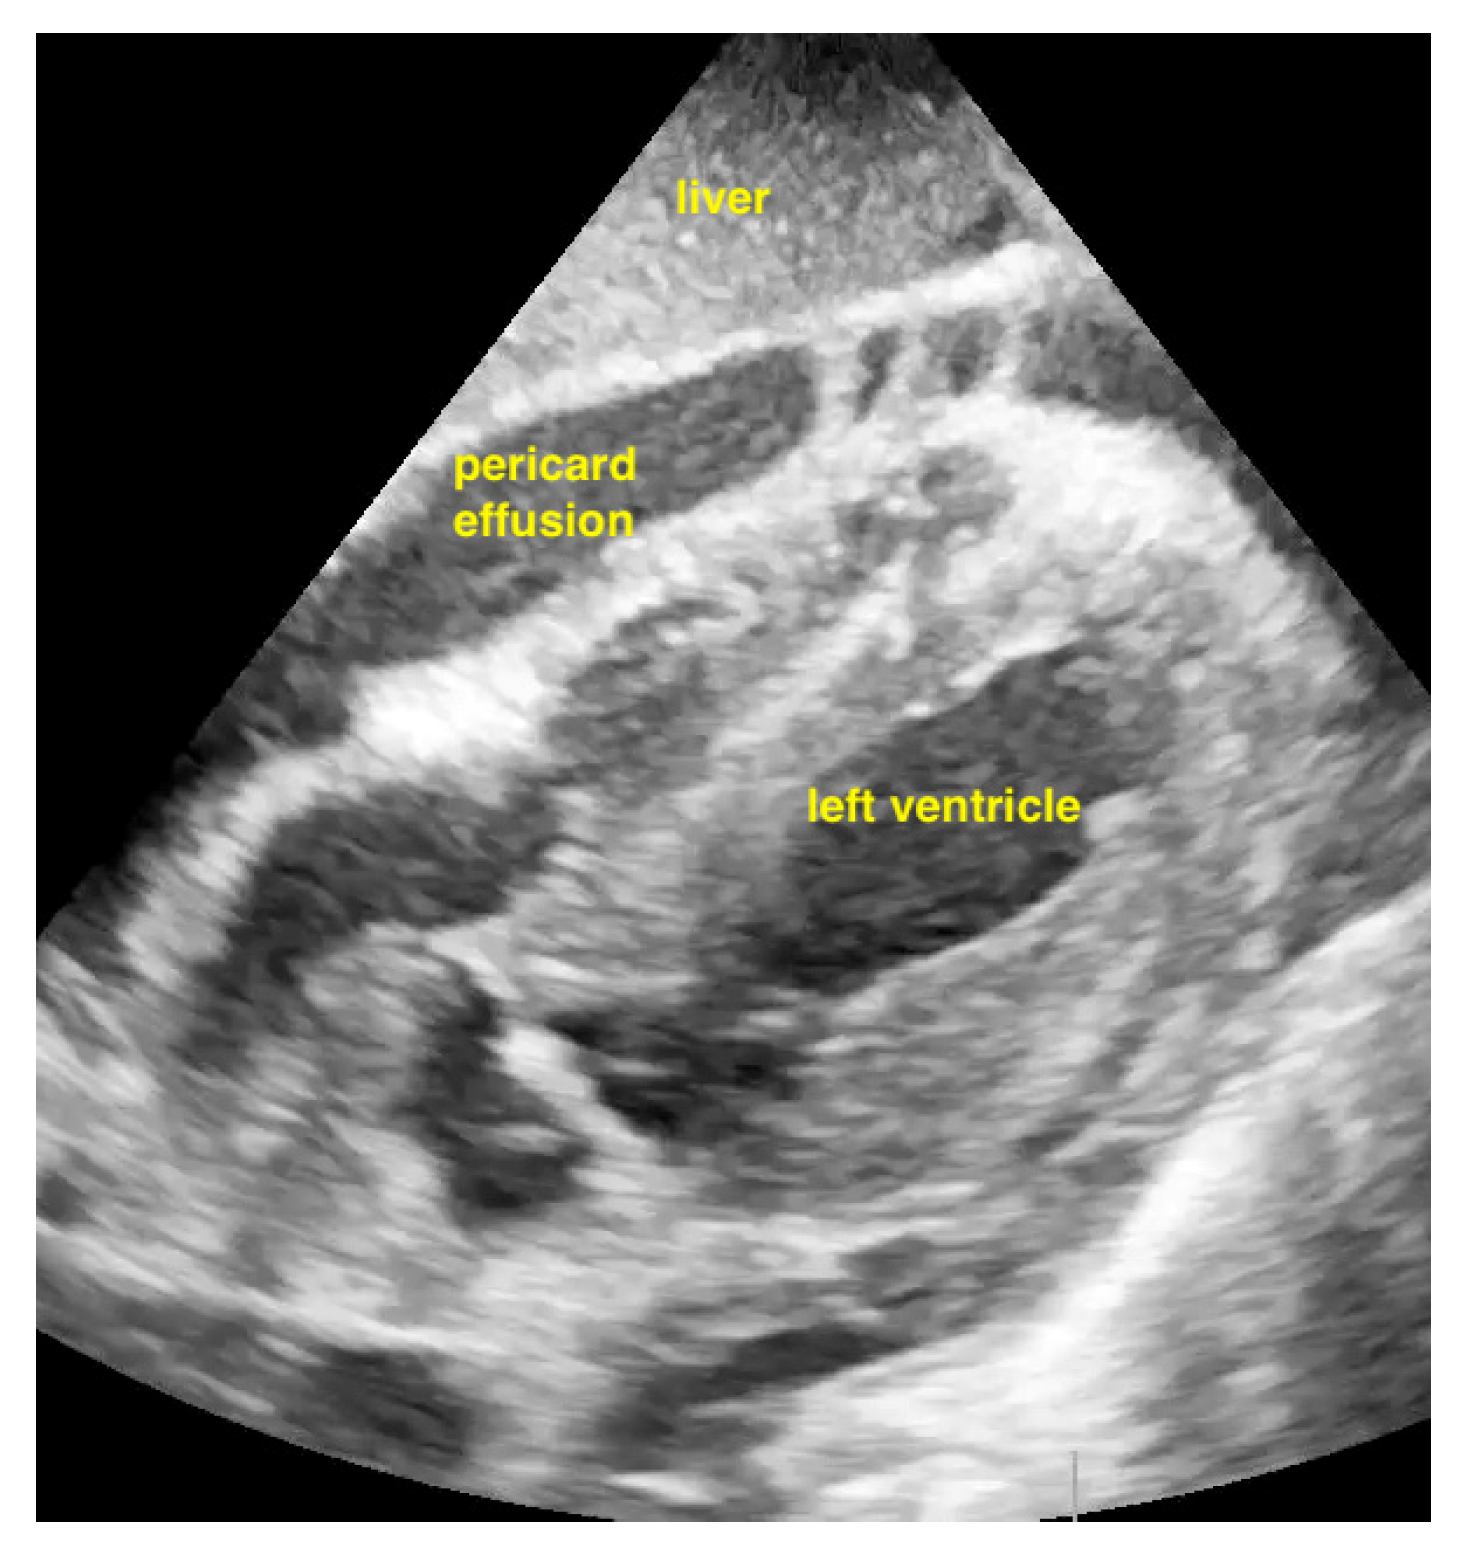

Figure 8.

Pericardial effusion in subxiphoidal view.